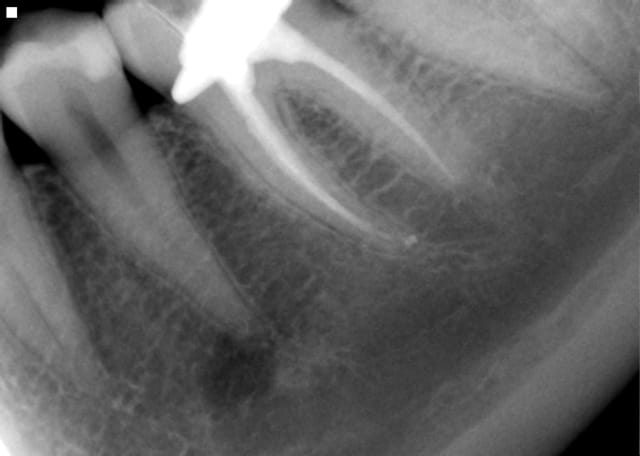

Bon, je fais pas bcp d'endo, et pas de molaire depuis 5 ans.

Donc je poste pas bcp de cas en endo...mais cette semaine, j'ai fais une molaire ! avec le Wave one, 1er essai clinique, j'avais le moteur depuis l'été, mais je continuais avec mes Protaper, question de ne pas avoir trop d'inventaire de limes, car avec 1 endo par semaine, parfois 2, le stock de Protaper descend pas trop vite...

Une gentille 36 pas difficile, 1 heure, avec Wave-one.

Je suis pas rapide, et je prend le temps de placer la digue.

En gros, ça fonctionne bien le wave-one.

Aller, lachez-vous les cadors de l'endo...

Ensuite, CCM, CCC, onlay, IC ?

Je sais , la radio est moche...On ne voit pas la portion distale de la dent, très abimée.